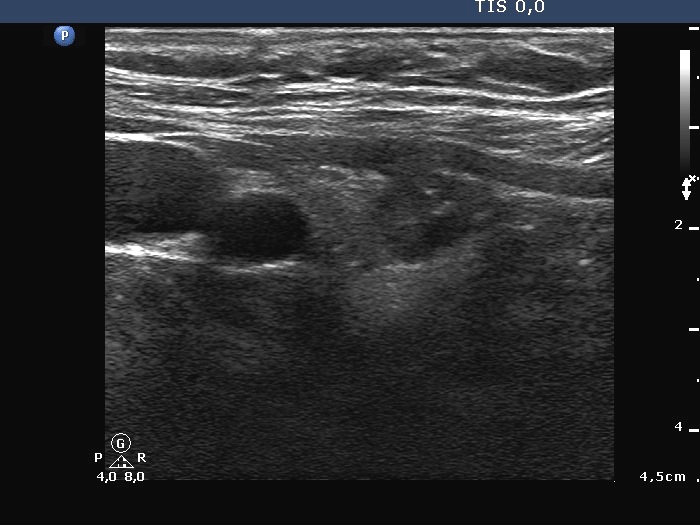

Thyroid cancers - case 959 (ultrasonographic picture 2)

Right lobe, longitudinal scan.